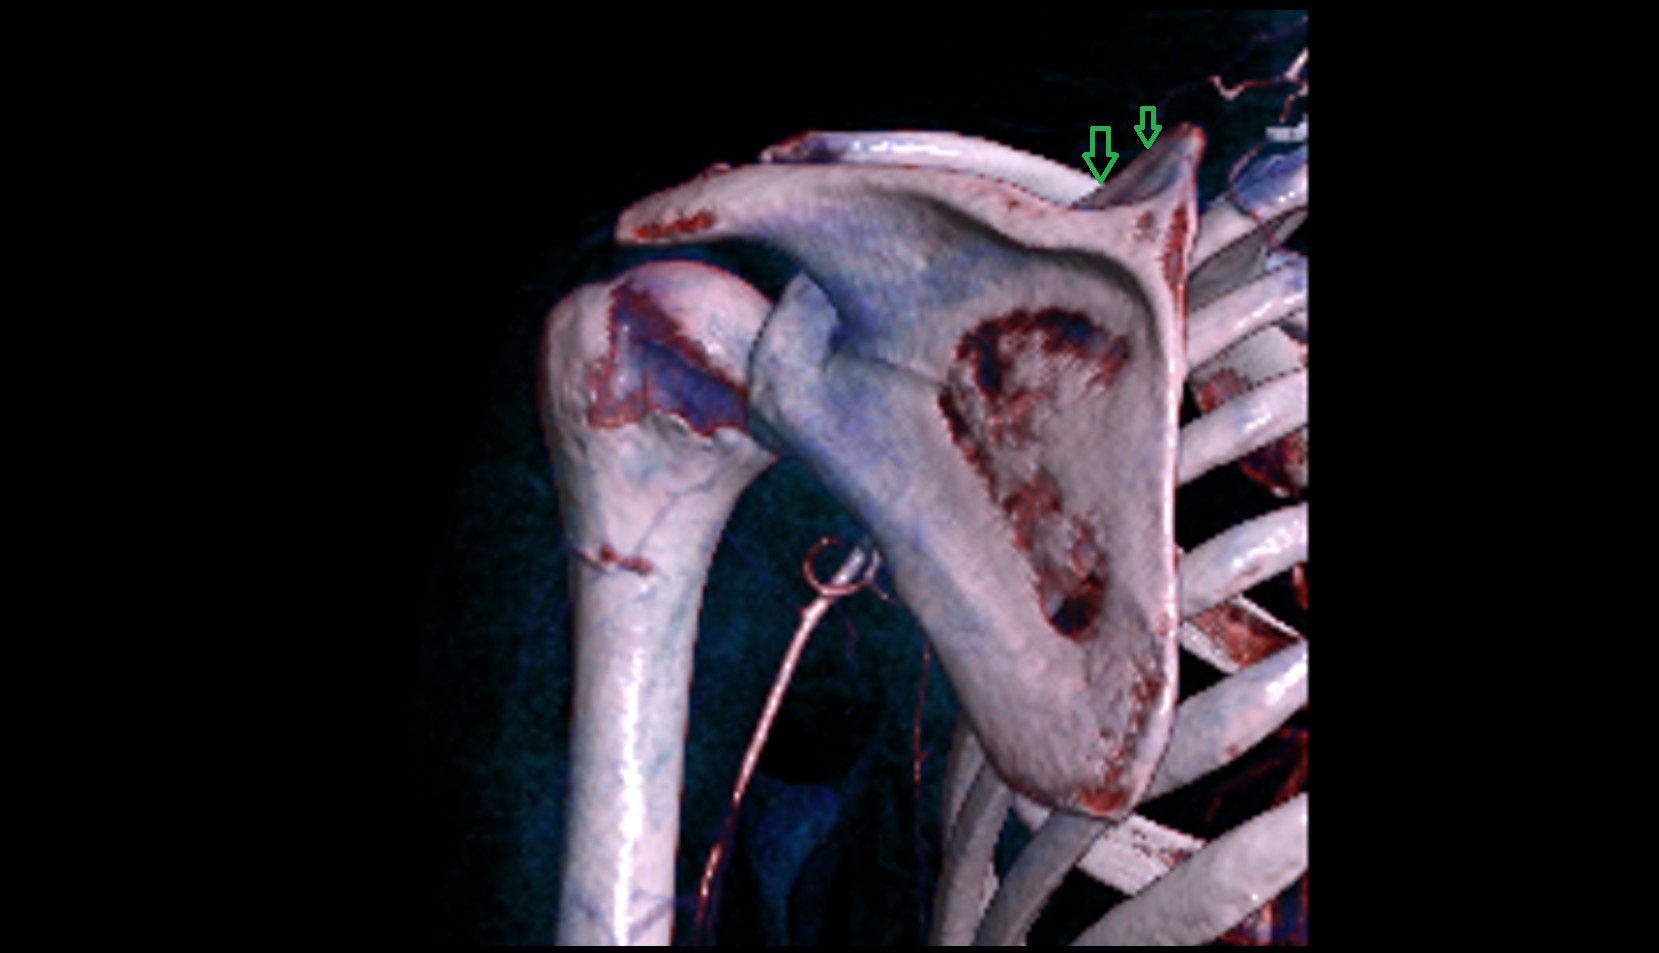

- Spine of scapula

- Acromion process of scapula

- Coracoid process of scapula